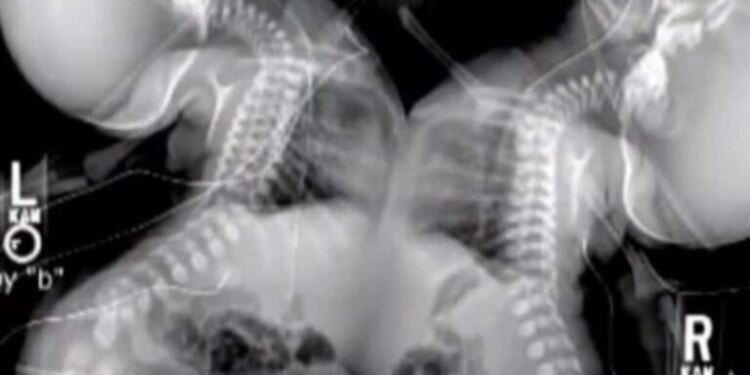

Τα δίδυμα ήταν ενωμένα στο στέρνο τους, στο διάφραγμα, στο συκώτι και στην μεμβράνη γύρω από την καρδιά. Ο φόβος ότι τα μικρά κορίτσια δεν θα επιβίωναν τον διαχωρισμό, οδήγησε τους γιατρούς να συμβουλέψουν την 27χρονη να τερματίσει την εγκυμοσύνη.